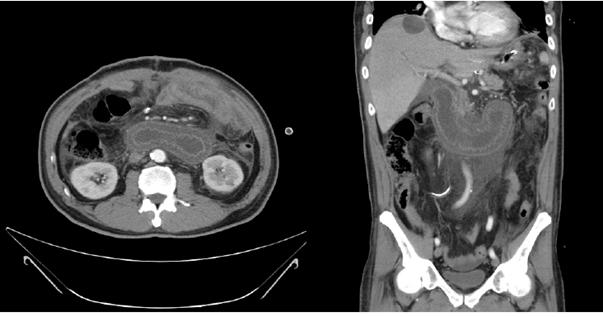

詳解

這題的解題核心在於病人有胃次全切除及Billroth II吻合術的病史,加上電腦斷層影像顯示一個極度擴張的輸入腸端(afferent loop),同時合併胰臟炎和膽道阻塞的生化指標。